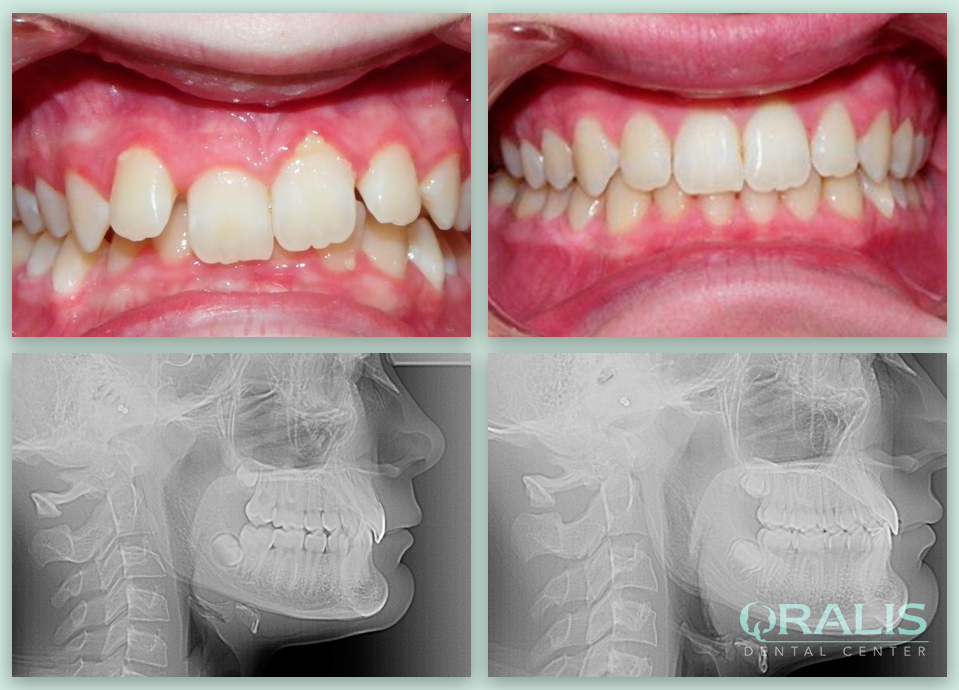

Αρχικά, γίνονται λήψεις φωτογραφιών, ακτινογραφιών ή οδοντιατρικών αποτυπώσεων των δοντιών σας. Οι συγκεκριμένες καταγραφές θα χρησιμοποιηθούν, προκειμένου να σχεδιαστεί ένα εξειδικευμένο πλάνο θεραπείας, το οποίο θα είναι λεπτομερές και προσαρμοσμένο ακριβώς στις ανάγκες σας από το γιατρό καθώς και από την επιστημονική ομάδα του, έχοντας κάνει ακριβή υπολογισμό των τελικών θέσεων που θα βρίσκονται τα δόντια σας μετά τη θεραπεία, καθώς και τη συνολική χρονική διάρκεια που θα έχει η θεραπεία.

Θεαματικά Αποτελέσματα με τα Αόρατα Σιδεράκια Invisalign

Μόλις ολοκληρωθεί η θεραπεία, το τελικό αποτέλεσμα θα είναι μια πολύ ευχάριστη έκπληξη για εσάς, παρόλο που το αποτέλεσμα του χαμόγελού σας με τα αόρατα σιδεράκια είναι απόλυτα προβλέψιμο, διότι τα αόρατα σιδεράκια Invisalign είναι κατασκευασμένα από ένα ειδικό, εξελιγμένο υλικό που εξασφαλίζει πάνω από 75% προβλεψιμότητα στη μετακίνηση των δοντιών. Η δυνατότητα να γνωρίζετε με ακρίβεια το αποτέλεσμα που θα πετύχετε, καθιστά τη διαδικασία πιο άνετη και ευχάριστη. Όσοι φοράτε τα αόρατα σιδεράκια Invisalign, νιώθετε αυτοπεποίθηση και άνεση από την αρχή, ενώ τα αόρατα σιδεράκια δεν σταματούν να διορθώνουν τα δόντια σας σε κάθε στάδιο της διαδικασίας.